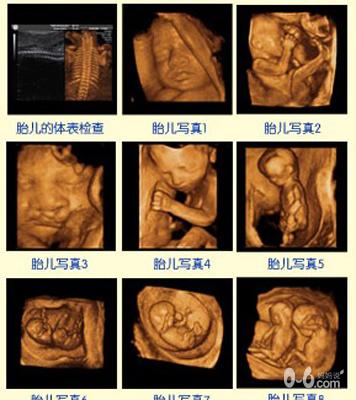

整个孕期主要分为三个阶段。怀孕后头3个月为第一阶段即胚胎阶段。这个阶段胚胎体积约有绿豆大小,但胎儿的一些主要器官,如大脑、眼睛、脊柱、肝脏、手臂和腿都已经开始发育,心脏也开始了跳动。

在第二阶段,孕妇可以感到胎儿在腹中活动,胎儿性别清晰可见,胎儿的组织已经发育完善,体重约1000克。从第二阶段起可以实施有计划的良性刺激式的胎教,但重点应该注意对胎儿的保护。怀孕的最后3~4个月是胎儿发育的第三阶段。在第三阶段,胎儿的体重继续增加,胎儿的肺已经发育完善,在出生后能够呼吸。